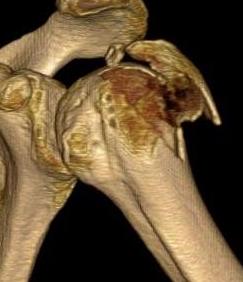

Mutch Classification

| Type A: Avulsion | Type B: Depression | Type C: Split |

|---|---|---|

| Horizontal fracture line | Fragment compressed inferiorly | Vertical fracture line |